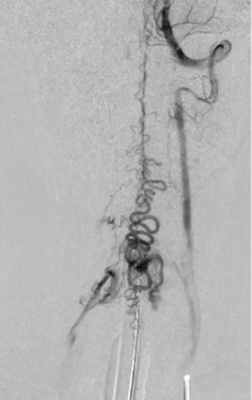

В стационаре выполнили МРТ шейного отдела позвоночника (рис. 1) и селективную спинальную ангиографию. По данным ангиографии, на уровне СVI—СVII позвонков выявлена спАВМ гломусного типа с наличием интранидальных аневризм и кровоснабжением из корешковых артерий, отходящих от левой позвоночной артерии и восходящей артерии шеи левого щитошейного ствола (рис. 2, а—в). Венозный дренаж осуществлялся в спинальные вены и венозное сплетение спинного мозга (рис. 3).

Рис. 3. Левосторонняя вертебральная ангиография, венозная фаза.

Определяется венозный дренаж артериовенозной мальформации.

Рис. 4. Минимальный остаточный кровоток в узле артериовенозной мальформации из афферентного сосуда, расположенного на уровень выше.